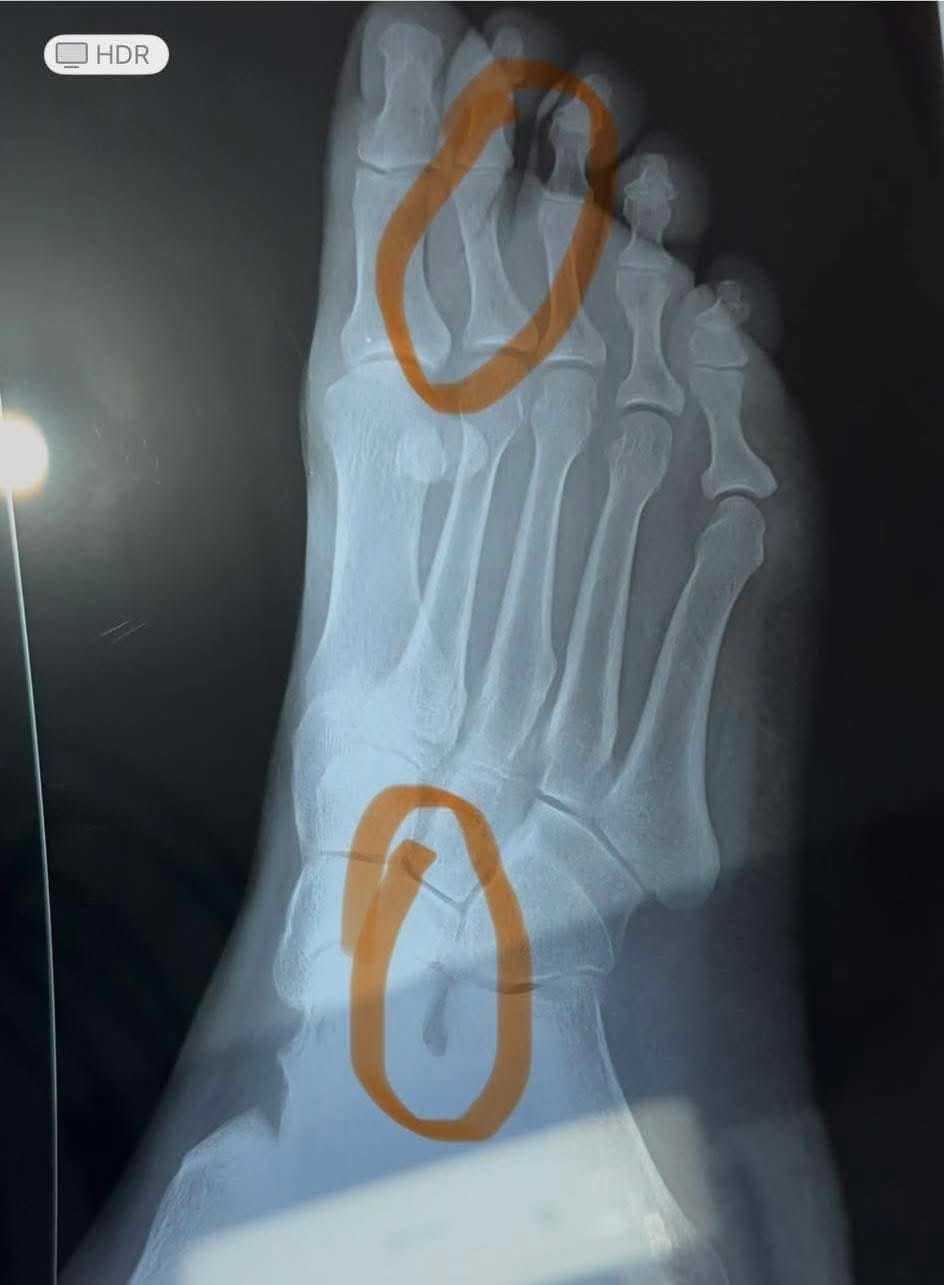

La Lic. Escalera mostró una radiografía de su pie derecho, confirmando las fracturas sufridas durante la agresión.

Evidencias. Escalera mostró una radiografía de su pie derecho, confirmando las fracturas sufridas durante la agresión. Además, anunció que en los próximos días revelará una imagen de su pie izquierdo como prueba adicional. "Aquí una muestra de mi pie derecho con las fracturas, para que no quede duda. Mañana les mostraré mi pie izquierdo, poco a poco", afirmó.